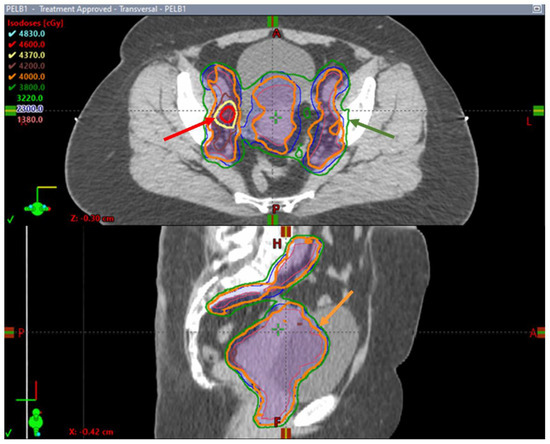

- Leung, E.; Gladwish, A.P.; Davidson, M.; Taggar, A.; Velker, V.; Barnes, E.; Mendez, L.; Donovan, E.; Gien, L.T.; Covens, A.; et al. Quality-of-Life Outcomes and Toxic Effects Among Patients with Cancers of the Uterus Treated with Stereotactic Pelvic Adjuvant Radiation Therapy: The SPARTACUS Phase 1/2 Nonrandomized Controlled Trial. JAMA Oncol. 2022, 8, 853. [Google Scholar] [CrossRef] [PubMed]

- Leung, D.E. Stereotactic Pelvic Adjuvant Radiation Therapy in Cancers of the Uterus II: A Phase II Randomized Controlled Trial; NCT04890912. 2021. Available online: https://clinicaltrials.gov (accessed on 6 July 2023).

- University of Chicago Phase I Safety Study of Whole Pelvic Hypofractionated Radiotherapy in Women with Endometrial Cancer; NCT04683653. 2023. Available online: https://clinicaltrials.gov (accessed on 6 July 2023).

- University of Utah RT-PACE: A Pilot Study of Adjuvant Hypo-Fractionated Radiotherapy for Non-Metastatic Cervical and Endometrial Cancer; NCT05139368. 2023. Available online: http://clinicaltrials.gov (accessed on 6 July 2023).

- Mittal, P. Postoperative Hypofractionated Radiation in Cervical and Endometrial Tumours: Phase II Study; NCT05857631. 2023. Available online: https://clinicaltrials.gov (accessed on 6 July 2023).

- Park, W. Postoperative Hypofractionated Intensity-Modulated Radiotherapy Endometrial Cancer: A Prospective Phase II Trial (POHIM_EM Trial); NCT05876130. 2023. Available online: https://clinicaltrials.gov (accessed on 6 July 2023).

- Memorial Sloan Kettering Cancer Center A Feasibility Study of Integrated Delivery of Hypofractionated Pelvic IMRT with Carboplatin and Paclitaxel in Stage III Copy-Number Low and Copy-Number High Subtypes of Endometrial Cancer; NCT05691010. 2023. Available online: https://clinicaltrials.gov (accessed on 6 July 2023).